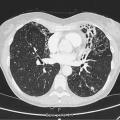

Seul un scanner thoracique haute résolution confirme le diagnostic anatomique : augmentation permanente et irréversible du calibre des bronches sous-segmentaires, cylindriques, variqueuses ou kystiques, localisées à un lobe ou diffuses. On élimine une autre cause de toux chronique comme un cancer bronchique. Toux, expectoration, infections bronchiques répétées + bronchectasies au scanner définissent le syndrome bronchectasique.